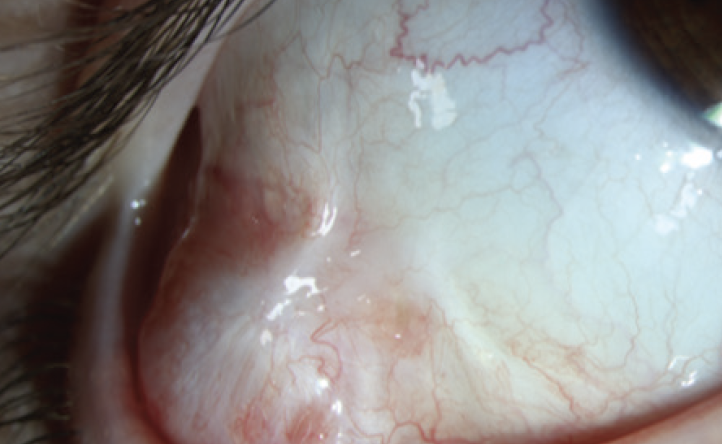

Histologic examination of the nodule showed conjunctival mucosa with a submucosally-based cystic lesion lined by 2 layers of columnar epithelium with focal decapitation secretion. The lesion was surrounded by a single myoepithelial layer (Figure 2). The findings were diagnostic of an apocrine hidrocystoma. The patient tolerated the procedure and was doing well at the 3-week follow up with no evidence of recurrence.